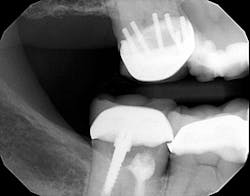

P.S. I counted seven pins.